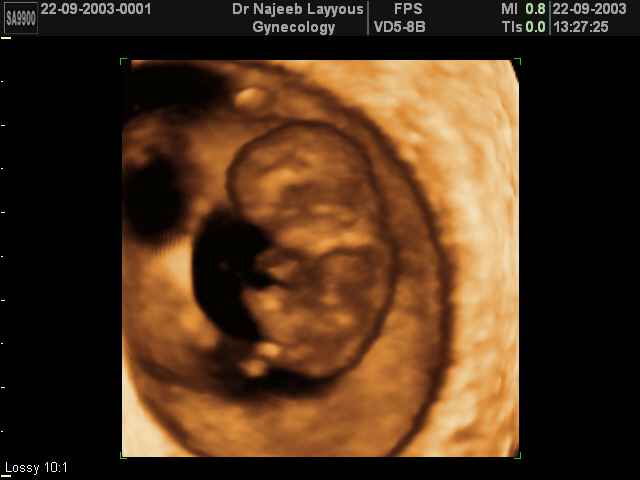

- First Trimester Ultrasound Photos

3D First Trimester Ultrasound Scan Photos ( Early Pregnancy Ultrasound Photos ) | Dr N Layyous